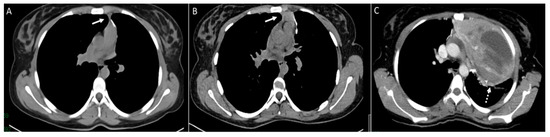

3. Pleura

4. Mediastinum and Hilum

5. Cardiac and Major Thoracic Vessels